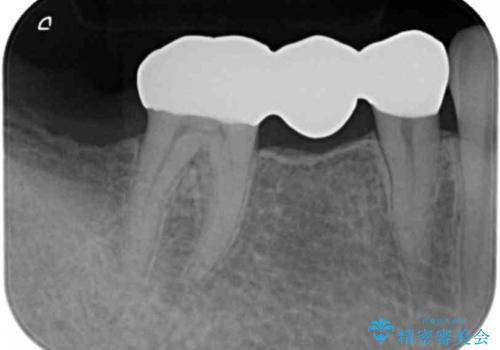

自然な仕上がりと咬み心地に喜んで頂けました。

「予算を抑えてしっかりとした治療が受けられた」とご満足頂けました。

プラークコントロール不良につき仮歯を精密に合わせても歯肉の腫脹を認めたため、工夫を凝らして精密な型取りを行うことで適合の良いクラウンを製作致しました。

クラウンの種類:ベレッツァクラウン